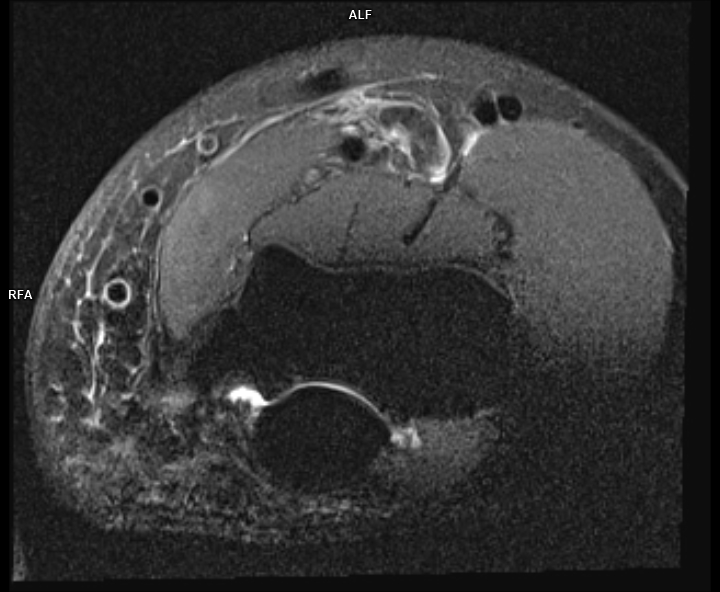

Figura 3: achiziție axial PD cu saturația grăsimii la nivelul cotului cu evidențierea tendonului de inserție inferioară a mușchiului biceps brachial ce este situat superior și are traiect serpiginos

Discuţie caz nr 52: ruptură inferioară / avulsia tendonului de inserție inferioară a mușchi biceps brahial este o entitate ce este 100% diagnosticată clinic care poate fi confirmată ecografic; examinarea IRM este recomandată pentru evidențierea retracției superioare a tendonului și pentru diagnosticarea leziunilor concomitente: bursită, formarea de hematom, modificări de semnal în corpul muscular, edem osos la nivelul tuberozității radiale.